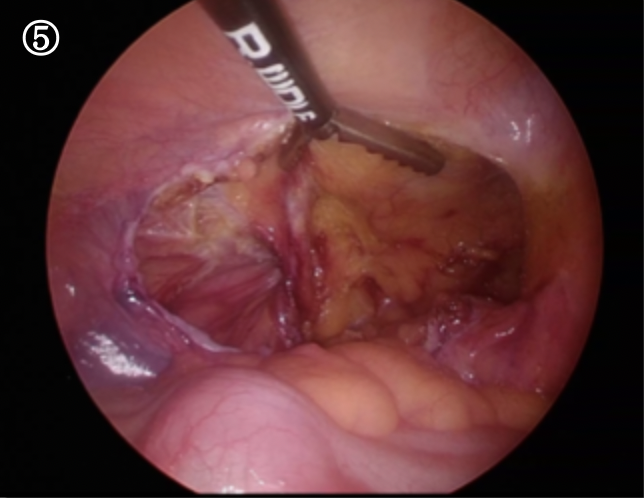

ぽっかりと大きなトンネルが見えます。これがヘルニア門と言われる穴です。腸の一部はこの門の奥に癒着し、完全には引き出すことが出来ませんでした

このヘルニア門に沿って腹膜という薄い膜を切っていきます。